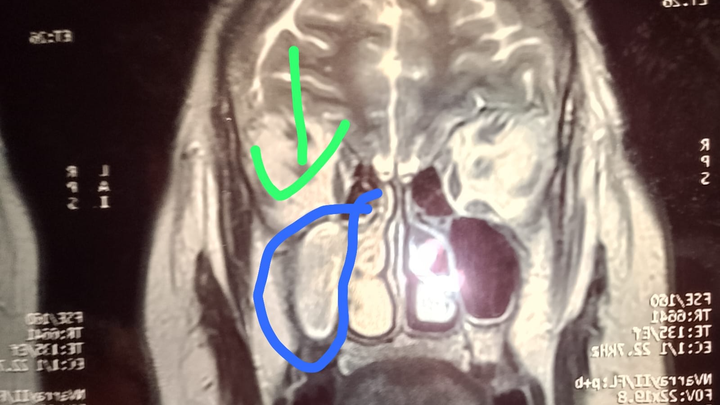

Hola, me llamo Claudia y estoy recaudando fondos para cirugía de craneo de mi mamá, en Cd. Juárez, le creció un tumor y oprimio nervio óptico del lado derecho el cual hizo que perdiera la vista de ese ojo. Hace más de un año está esperando cirugía por medio del IMSS, la cual no se a realizado por falta de equipo, viajo en 2 ocasiones ala ciudad de Torreón y ya estando en quirófano se canceló por falta de un aparato. Acudió a neurocirujano y comenta que si no se opera seguirá oprimiendo y es de riesgo ya que está en una arteria, es cirugía urgente la que necesita mi mamá ya que su vida corre peligro.